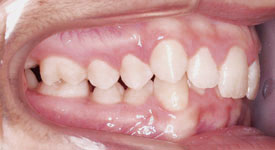

Crowding Front